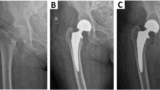

第27回日本骨粗鬆症学会の会場です.

最初に参加した『シンポジウム1 骨粗鬆症の予防と治療ガイドライン2025の概要』では, 1,000席はすべて埋まっていました. 今年10年ぶりに改訂されたガイドラインが紹介されました.

続く海外招待講演では, ロモソズマブの基礎研究に関する発表がありました.